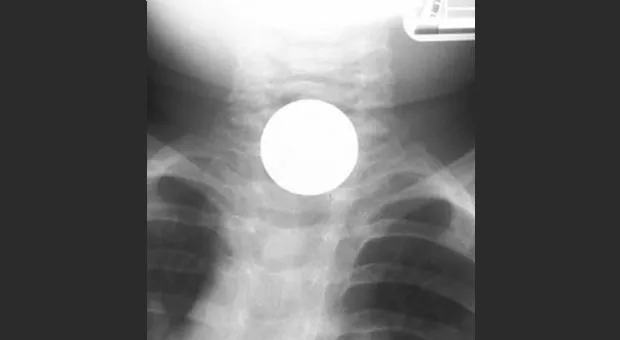

Иллюстрация №2: Инородное тело (монета) пищевода

Т.к. большинство истинных инородных тел рентгенконтрастны, диагностическим методом выбора является рентгенография (шеи, грудной клетки и живота) в нескольких проекциях (чаще фронтальной и боковой).